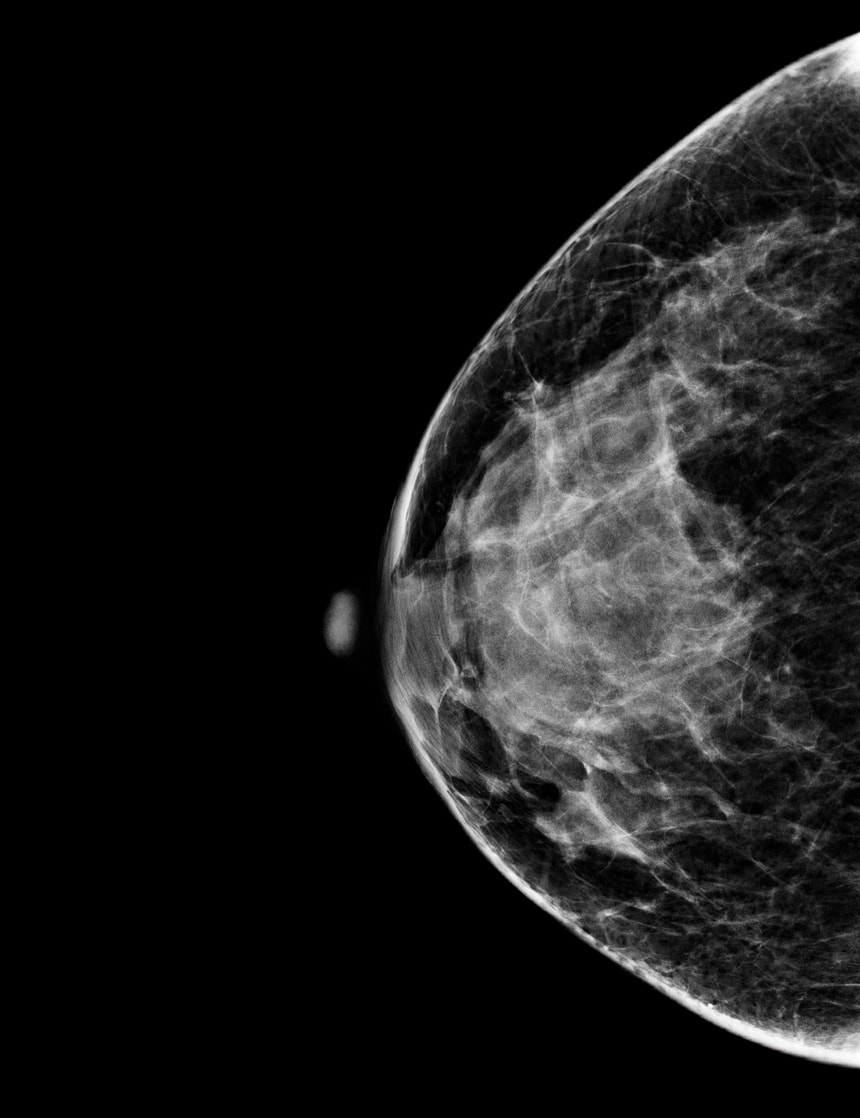

Menopausa potencia o desenvolvimento de cancro na mama

A redução do estrogénio provoca alterações nas células do tecido mamário. Pela primeira vez, cientistas traçaram um mapa inédito da dimensão dessas alterações, que permite perceber, como nunca, o mecanismo celular.

Foto: Science Photo Library via AFP